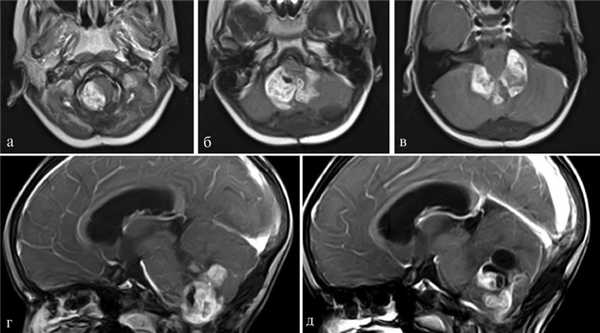

Пациентка Д., 4 года. Госпитализирована в институт 15.09.14. Диагноз: рецидив анапластической эпендимомы ствола и IV желудочка. Окклюзионная гидроцефалия. Состояние после удаления опухоли 20.06.12. Состояние после ЛТ и ПХТ (рис. 3). Рис. 3. Наблюдение 3: пациентка Д. Дооперационное МРТ-исследование, режим T1 с контрастом. а, б, в — аксиальная проекция; г, д — сагиттальная проекция. Пояснения в тексте.